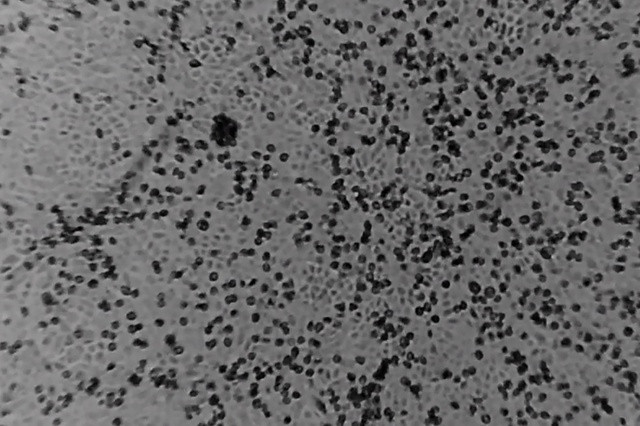

Các nhà khoa học Thụy Sỹ phát hiện sức mạnh chống virus của đường ảnh 1Phương pháp này có thể áp dụng, chẳng hạn như đối với virus corona mới ở Trung Quốc. (Nguồn: Keystone)

Các phân tử đường biến đổi thu hút virus trước khi vô hiệu hóa chúng. Bằng cách phá vỡ lớp ngoài của virus, chúng quản lý để tiêu diệt qua tiếp xúc đơn giản, thay vì chỉ ngăn chặn sự phát triển của virus. Cơ chế này dường như hiệu quả với tất cả virus có liên quan.

Các nhà khoa học đã có thể chứng minh điều này đối với các virus về nhiễm trùng đường hô hấp và herpes.